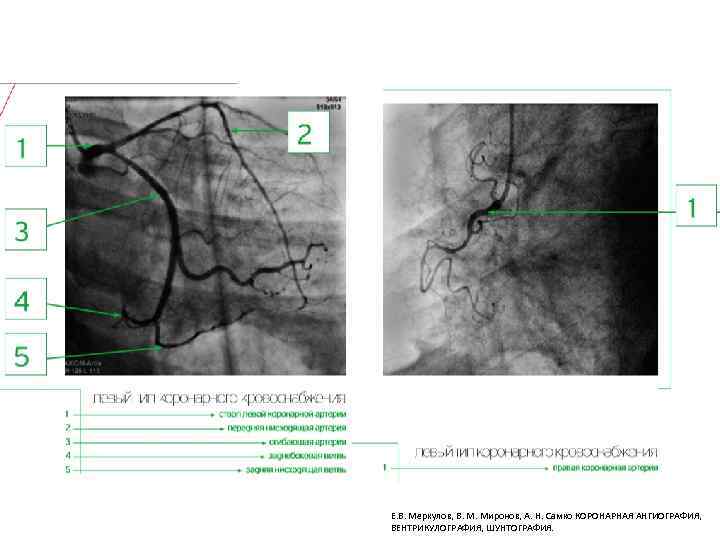

Типы кровоснабжения сердца Е. В. Меркулов, В. М. Миронов, А. Н. Самко КОРОНАРНАЯ АНГИОГРАФИЯ, ВЕНТРИКУЛОГРАФИЯ, ШУНТОГРАФИЯ.

Е. В. Меркулов, В. М. Миронов, А. Н. Самко КОРОНАРНАЯ АНГИОГРАФИЯ, ВЕНТРИКУЛОГРАФИЯ, ШУНТОГРАФИЯ.